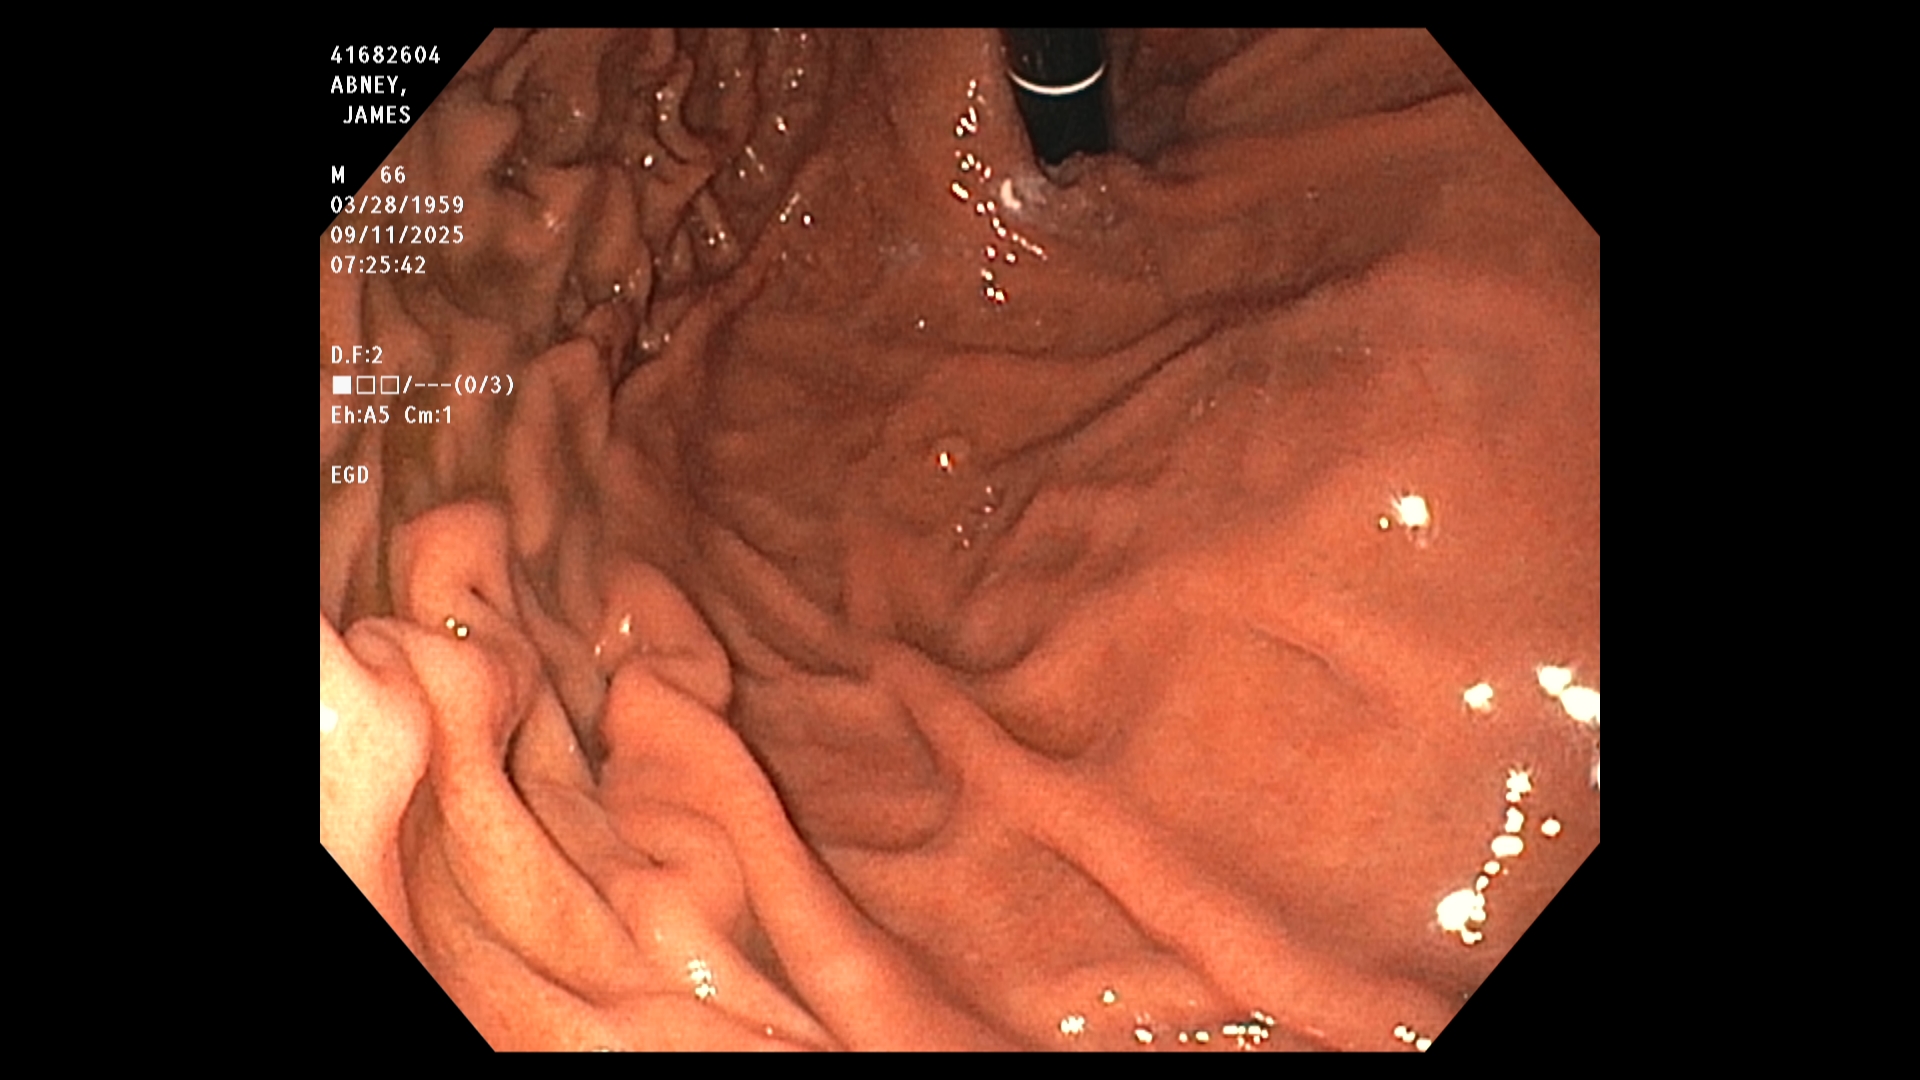

The endoscopist in this study generated a series of images showing the stomach, duodenum,

duodenal bulb, and esophagus, among others. The stomach was imaged first. The image is a

retroflexed view, in which the endoscope was passed through the stomach and the camera

turned backward to take the image, which shows both the stomach and an upstream portion of

the endoscope. The endoscope was next passed into the duodenum, farther down the GI tract,

and then withdrawn while care was taken to observe mucosal detail.

The EGD results in this study were good. In particular, the endoscopist stated that all observed

structures appeared normal and that there was no evidence of any damage, including acid-

reflux damage.